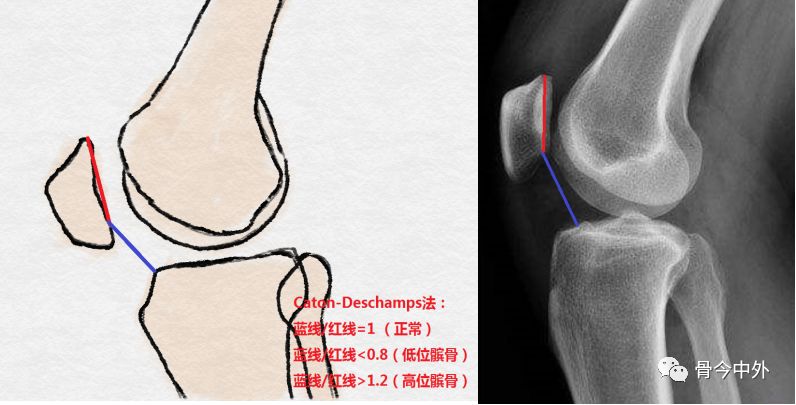

髌骨高度

最常用的三种测量方法:

Canton-Deschamps

-髌骨关节面最低点到胫骨平台前上角(蓝线)

-髌骨关节面长度(红线)

判断标准:

指数 | 正常范围 | 高位髌骨 | 低位髌骨 |

Insall-Salvati index | 1 | >1.2 | <0.8 |

Modified Insall-Salvati | 1.25 | >2.0 | |

Caton-Deschamps Index | 1 | >1.3 | <0.6 |

Blackburn-Peel Index | 0.6 | >1.0 | <0.8 |